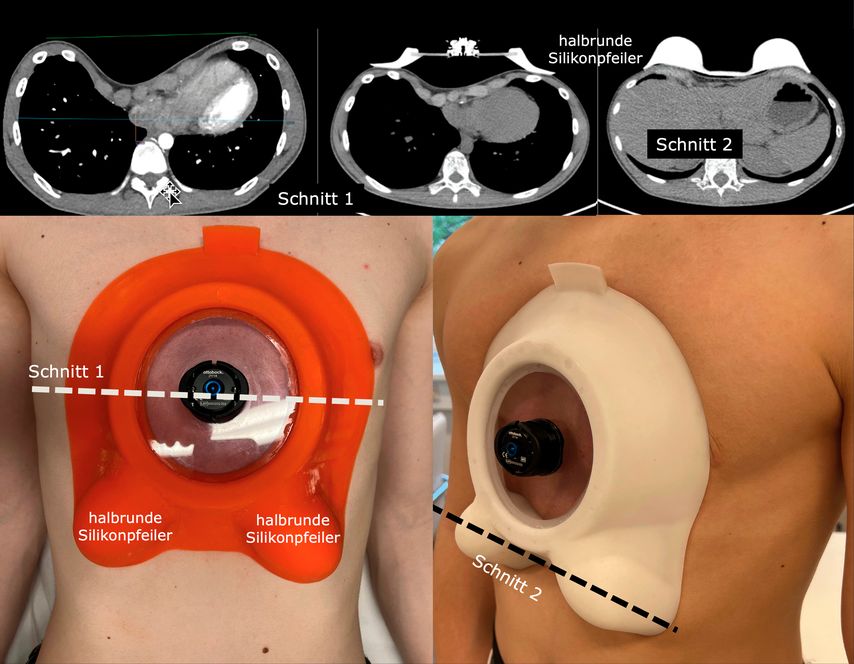

Für die spezielle Situation, in der vorgewölbte untere Rippenbögen („flared ribs“) vorhanden sind, bewährt sich als aktuelle innovative Entwicklung die Y-förmig gestaltete Unterdruck-Überdruck-Saugglocke® (Abb.4), die einerseits den Trichter abflacht, gleichzeitig aber auch eine Kompression auf vorspringende untere Rippenbögen (Abb.5) ausübt und die komplette Umformung provoziert. Alle Saugsysteme machen den Brustkorb grundsätzlich beweglicher.

Abb. 4: Unterdruck-Überdruck-Saugglockentherapie bei Trichterbrust mit vorspringenden Rippenbögen mit der Y-Saugglocke® (Fa. Götz Orthopädietechnik St. Pölten/Fa. Sanag Tulln)

Die Kompression auf vorspringende Areale der Thoraxwand, wie sie z.B. im Rahmen einer gemischten vertikalen Kiel-Trichterdeformität auftritt, kann durch zusätzliche, individuell angepasste Silikonkissen innerhalb der Saugglocke behandelt werden (Abb.6).

Abb. 6: Bei vertikaler Kiel-Trichterdeformität Unterdruck-Überdruck-Saugglockentherapie mit eingesetztem Silikonkissen als Pelotte in einer Y-Saugglocke® (Fa. Götz Orthopädietechnik St. Pölten/Fa. Sanag, Tulln)